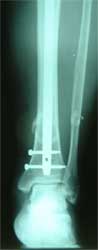

长骨干的力学特点是负重,两端为大关节,附着肌肉力量较大,应力突出。钢板内固定时广泛的软组织剥离,容易损伤血液循环和关节功能。 带锁髓内钉在骨组织和钉体之间提供较均匀的弹性应力分布,避免,抗旋转作用强于可屈髓内钉,不需外固定,对断端稳定性好,可早期功能锻炼。有优于钢板、外固定架和可屈髓钉的特点,已经成为治疗新鲜长骨干骨折的有效方法 。 但在长骨干骺端骨折、骨不连时,由于锁钉距离主钉孔较远,约在1.5-5.5厘米范围内,锁定骨折端有困难。 ZIMMER公司新型的带锁髓内钉可用于治疗长骨干骺端骨折、骨不连。由于锁钉距离主钉孔较近,约在0.5-3.5厘米范围内,可以满意锁定长骨干骺端骨折、骨不连。

胫骨中段、远端多段骨折,如果采用钢板固定,切口会很大,剥离骨膜,严重影响血运。由于中段、远端多段骨折,外固定架也难于获得满意固定效果。

采用特殊的带锁髓内钉固定多段骨折,可以采用闭合穿针方法,即不切开骨折部位的软组织,不破坏血液循环,不用外固定,可以早期锻炼关节,关节功能好,骨折愈合快。